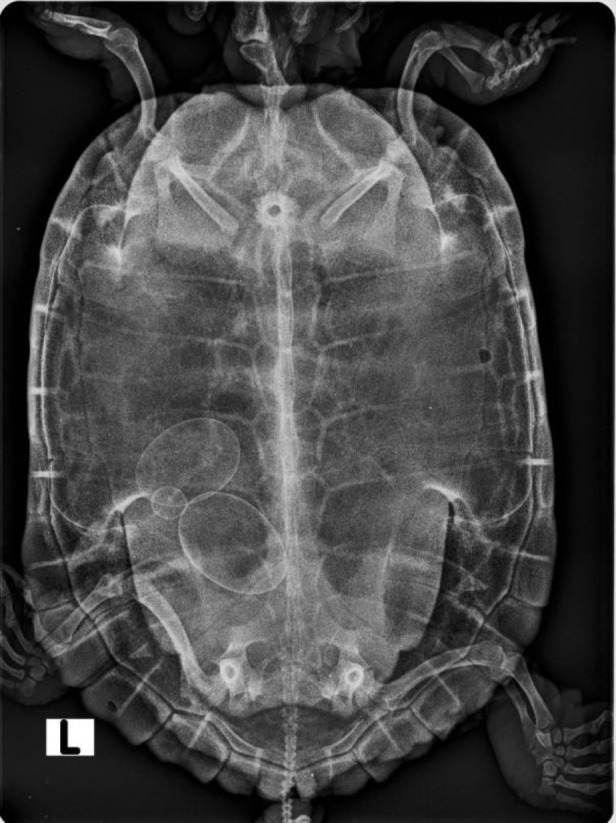

Case description: Three owned red-eared sliders were separately presented with a history of recent lethargy, inappetence, dyspnea, and restlessness.

Findings/treatment and outcome: In these three cases of chronic dystocia, a ketamine and medetomidine combination was used to achieve anesthesia induction for surgical treatment. Additionally, intrathecal administration of lidocaine was performed to achieve a potential analgesic effect in deeper intracoelomic reproductive organs. Preoperative changes in blood parameters were observed in one animal, suggesting abnormal kidney function. The same animal showed signs of resedation postoperatively, prolonged recovery, and had a fatal outcome 48 h after the surgery with signs of kidney damage in histopathological evaluation. In the recovery period, none of the surviving animals (n=2) showed neurological or respiratory complications that could be associated with subcarapacial sinus anesthesia administration or intrathecal local anesthesia.